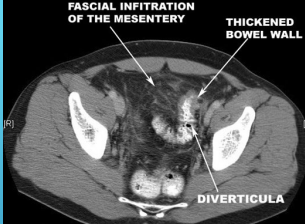

CT, contrast, thickening, diverticula, colonoscopy, perforation, 6-8

Diverticulitis: Diagnosis

-Labs → CBC

-Imaging → Abdominal __ with oral/IV ________ (preferred imaging)

Localized bowel wall ___________ (>4mm)

Increases soft tissue density within pericolonic fat (fat stranding)

Presence of _________

Can also find complications if present

-___________ should be avoided during acute diverticulitis d/t risk of _________

-After resolution of symptoms (_-_ weeks) a colonoscopy can be performed if the pt hasn’t had one within the previous year